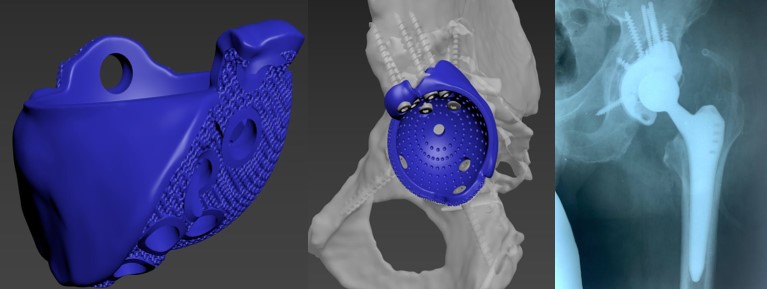

Приклад заміщення дефектів кісток тазу при ураженні пухлиною. Складне індивідуальне ендопротезування кульшового суглоба

Пацієнт С-к Роман Михайлович, 1975 рік. Травма в результаті ДТП (7.10.2023 р.) – перелом заднього краю лівої кульшової западини зі зміщенням. Післятравматичний лівобічний коксартроз 4 ст., стан після МОС заднього краю лівої кульшової западини пластиною та гвинтами. Згинально-привідна контрактура зліва. Наслідки ушкодження лівого сідничного нерва в лівій сідничній ділянці. Стан після встановлення ЕСС “НейСі-3М” на малогомілковий (CPN) та великогомілковий (TN) нерви в н/3 лівого стегна.

Операція: Вилучення металофіксаотора. Повна артропластика лівого кульшового суглоба з індивідуальним ацетабулярним компонентом

Пацієнт С-к Роман Михайлович, 1975 рік. Травма в результаті ДТП (7.10.2023 р.) – перелом заднього краю лівої кульшової западини зі зміщенням.

Післятравматичний лівобічний коксартроз 4 ст., стан після МОС заднього краю лівої кульшової западини пластиною та гвинтами. Згинально-привідна контрактура зліва. Наслідки ушкодження лівого сідничного нерва в лівій сідничній ділянці. Стан після встановлення ЕСС “НейСі-3М” на малогомілковий (CPN) та великогомілковий (TN) нерви в н/3 лівого стегна.

Спроектована та імплантована індивідуальна, пориста, титанова, 3D-друкована кульшова западина, фіксована гвинтами.